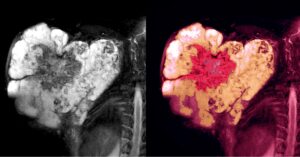

هو سرطان يحدث تحت الجلد ويكون في أعضاء الأنسجة الرخوة مثل: الطبقات الدهنية، العضلات، الأوعية الدموية، الأعصاب، وما إلى ذلك، حيث أنّ آلية التشخيص والعلاج تختلف من نسيج إلى آخر، باختلاف شكل النسيج الرخو في كلّ منطقة من مناطق الجسم.

أمّا في ما يخصّ أعراض مرض ساركوما الأنسجة الرخوة، فتكمن في ظهور كتل أو نتوءات في أجزاء مختلفة من الجسم، مثل الذراعين أو الساقين ومناطق أخرى في الجسم، إذ أنّ تلك النتوءات تزداد في الحجم يوماً بعد يوم ما قد يزيد من خطورة الحالة. وقد تكون مؤلمة في بعض الحالات، فإذا كانت هناك جروح أو تقرّحات، تصبح مزمنة ولا تلتئم بسهولة.